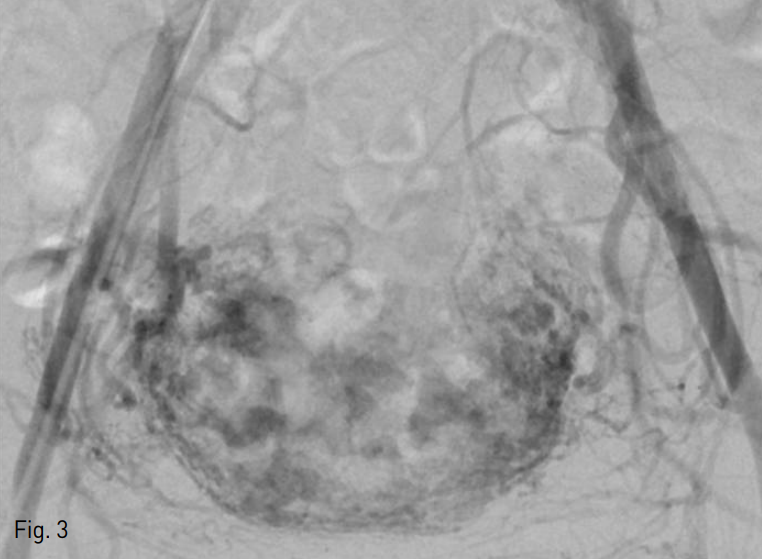

질식 초음파상에서 자궁에 큰 혈관성 종괴가 발견되었다. 종괴 내부에는 무에코성의 불규칙적인 관상 구조물이 관찰되었는데 이들은 색도플러 초음파에서 여러 방향의 빠른 속도를 보이는 동맥혈류를 가진 혈관 덩어리였다 (Fig. 1). 이후 복부전산화 단층촬영을 시행하였고, 자궁의 앞쪽 벽과 자궁강을 침범하는 장경 8cm 크기의 종괴를 확인할 수 있었다. 종괴 내부에는 비정상적인 혈관으로 보이는 구불구불한 관상의 조영증강 구조물들이 있었고, 자궁주변에 동맥기에서 조기 조영증강을 보이면서 비정상적으로 비대해져 있는 정맥도 관찰되었다 (Fig. 2).

Fig. 2

CT scan shows a large low density mass with highly enhancing, serpinginous tubular structures. Multiple prominent engorged veins (arrows) are observed in both parametrium.